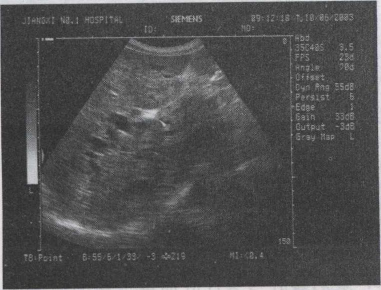

34.男,47岁,上腹部疼痛不适、腹胀,皮肤巩膜黄疸,进行性加重,皮肤瘙痒。声像图如图所示,最可能的诊断为()